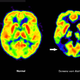

Bisherige Alzheimer-Therapien behandeln nur Symptome der Krankheit, nicht ursächliche Prozesse im Gehirn. Das ist bei Lecanemab anders: Der Antikörper richtet sich gegen Amyloid-Ablagerungen im Gehirn und soll dadurch den Verlauf der Krankheit verlangsamen. Um Heilung oder Verbesserung geht es allerdings auch bei diesem Wirkstoff nicht, ein solches Mittel ist weiterhin nicht in Sicht.

Die erfassten Schwellungen und Mikroblutungen im Gehirn blieben überwiegend ohne Symptome und wurden zumeist erst durch bildgebende Verfahren wie Magnetresonanztomographie (MRT) bemerkt. Insbesondere bei wiederholtem Auftreten drohen jedoch eine verminderte Gehirnleistung oder Koordinationsschwierigkeiten. Mikroblutungen gelten zudem als Risikofaktor für größere, potenziell lebensbedrohliche Hirnblutungen.

Erwähnt wird im Fachjournal «The BMJ» zudem die in den Studien zu den Wirkstoffen gemachte Beobachtung, dass die Anti-Amyloid-Medikamente das Gehirn merklich schrumpfen lassen. Was es damit auf sich hat, ist bisher noch vollkommen unklar.